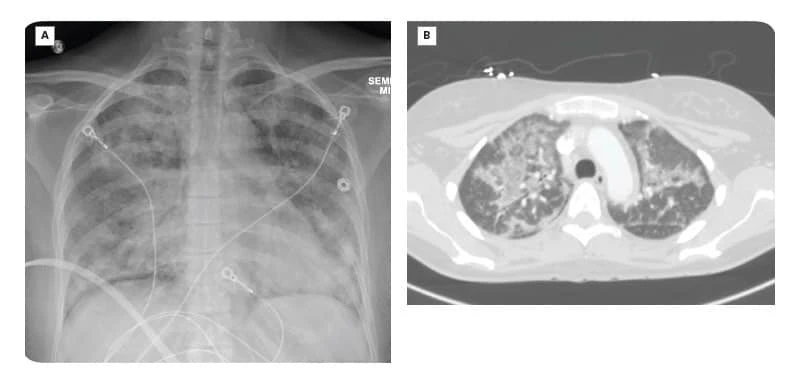

Hình ảnh chụp X-quang phổi của nữ bệnh nhân cho thấy bên phổi trái bị xẹp. Ảnh: BVCC.

Các bác sĩ chỉ định làm xét nghiệm, người bệnh được chẩn đoán viêm phổi nặng, phổi trái xẹp, nguyên nhân là hút thuốc lá điện tử.

"Cô gái còn trẻ nhưng tổn thương ở phổi lại rất nặng nề, không khác gì ở người cao tuổi. Tình trạng bệnh diễn biến phức tạp, chúng tôi phải điều trị bảo tồn tối đa chức năng phổi của người bệnh”, bác sĩ điều trị cho bệnh nhân thông tin.